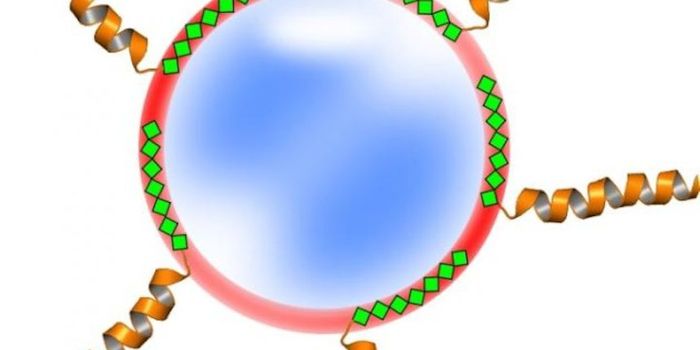

APR 20, 2015Cell & Molecular BiologyFastening protein-based medical treatments to nanoparticles isn't easy.